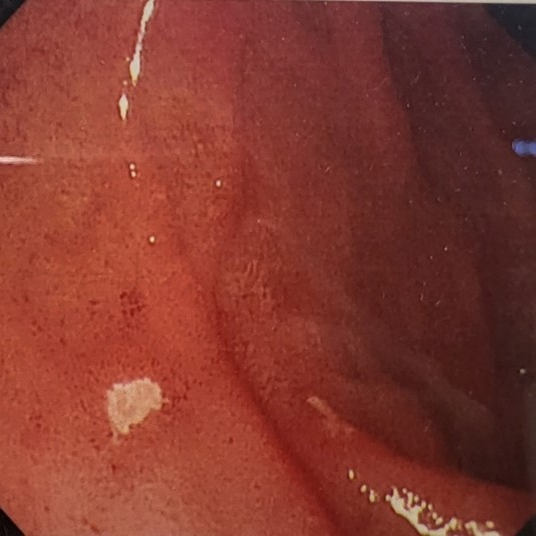

역류성식도염